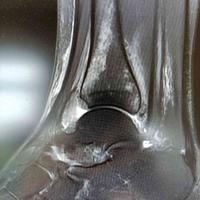

跟骨动脉瘤样骨囊肿

查看图片需登陆

跟骨动脉瘤样骨囊肿...

由 medjpg 发表于 2026-03-24 22:32